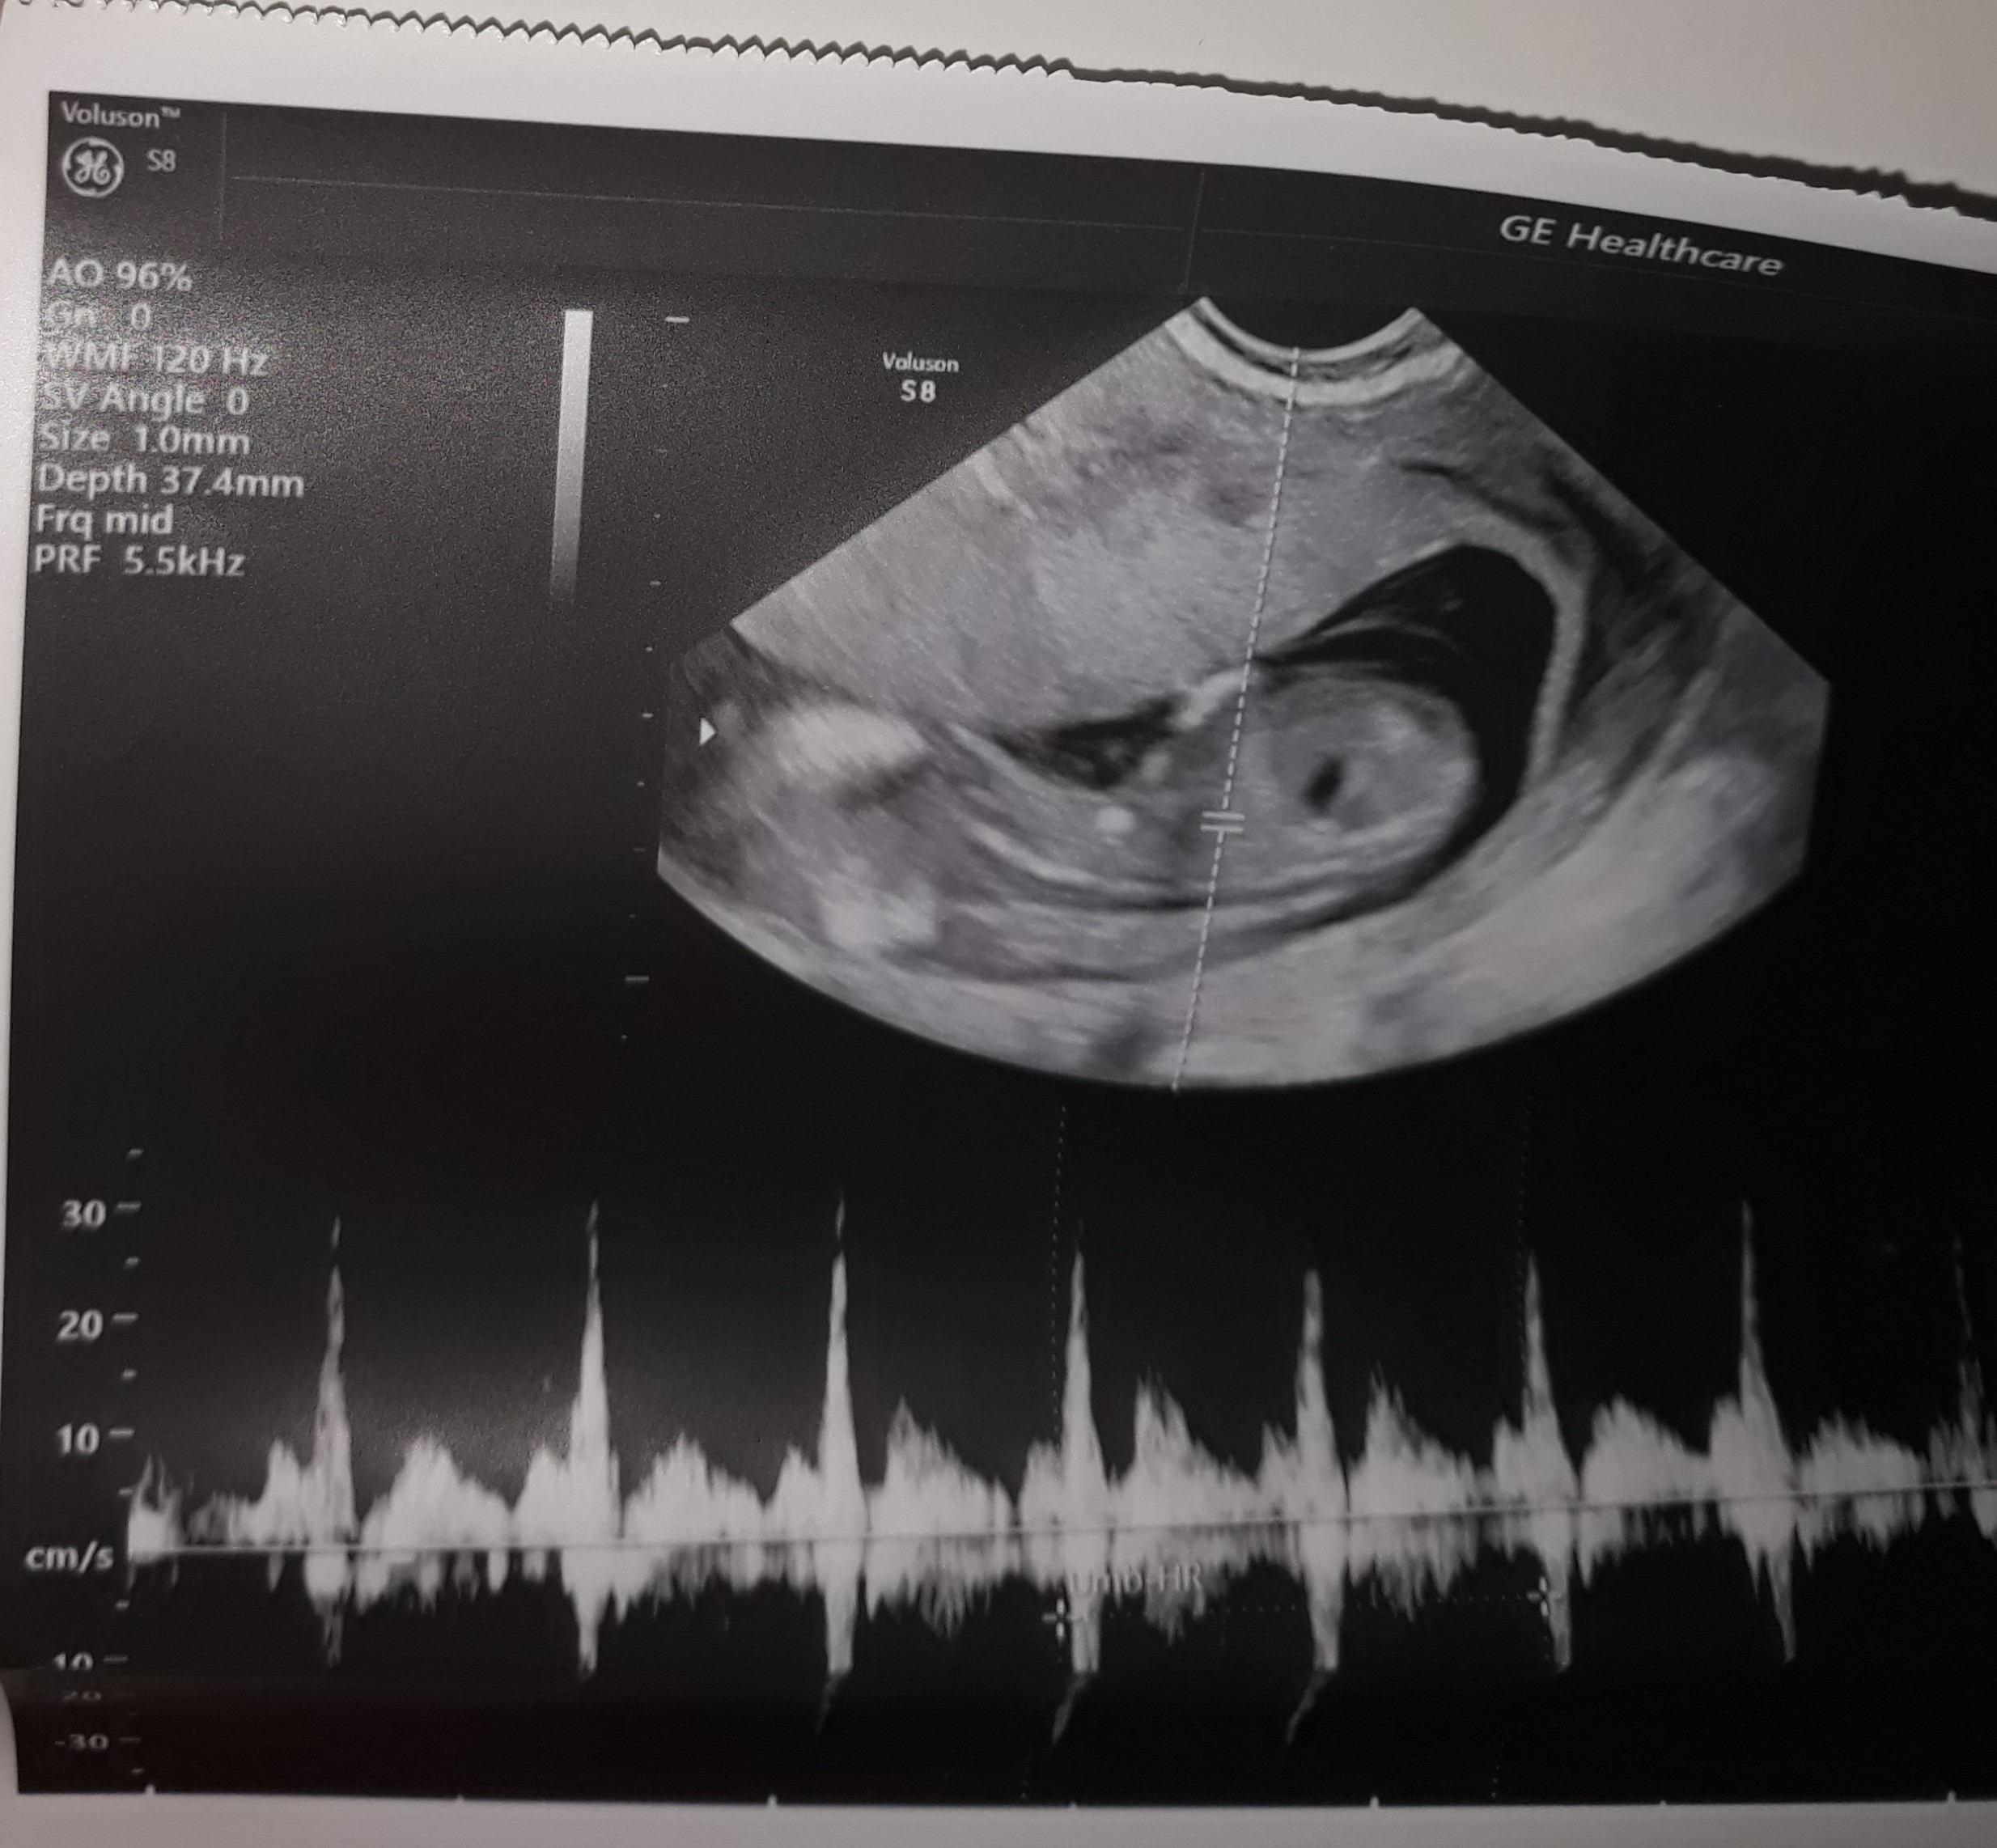

Usg w 13 tc

Witam , wiem , że to może głupie pytanie , ale to moja 1 ciąża i się wszystkim przejmuję. Dlaczego te usg jest takie dziwne , zamazane ? Wogóle nie widać kształtów dziecka. Czy któras też tak miała?

Tylko takie zdjęcie masz ? Wygląda trochę jakby była próba łapania przezierności, ale dziwnie nie bokiem tylko tyłem, to drugie chyba jest z pomiarem crl i wygląda na pierwszy rzut oka lepiej, ale też bez szału. Dzidzuś się mocno ruszał? Słabe to zdjęcie, a to ważne usg, masz opis taki porządny ze wszystkimi pomiarami itd.? Jak nie to może powtórz u kogoś z lepszym sprzętem...